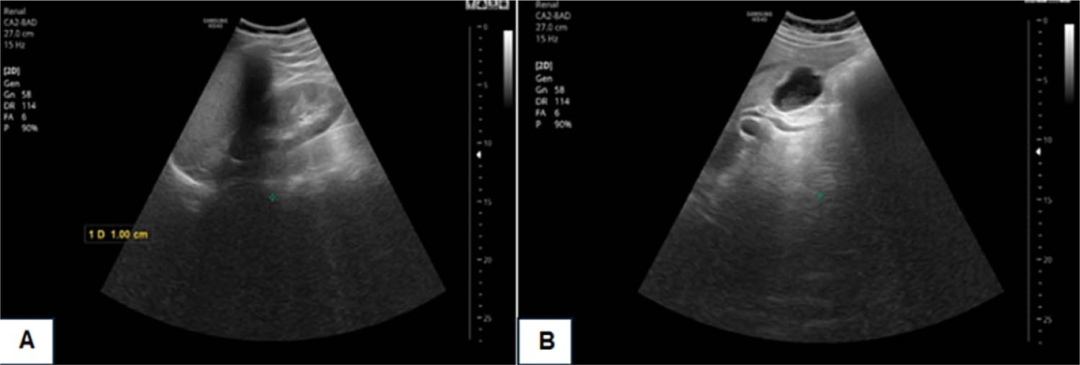

- 中年女性无症状肝脏多发病灶,原因为何? 医脉通-临床病例平台患者女,45岁,因影像学检查偶然发现肝脏多发病灶就诊。患者无相关症状,体格检查正常。……